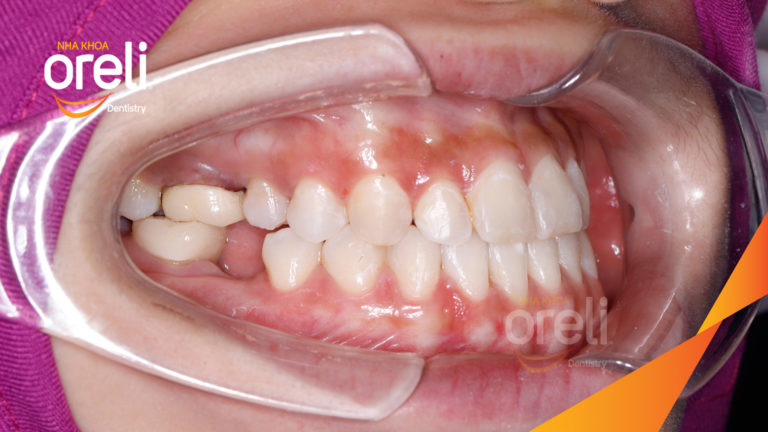

Ca niềng răng đặc biệt: kéo răng 7, 8 thay thế 3 răng 6 bị hư tại Oreli Niềng răngDi gần răng 7 8 Xem thêm